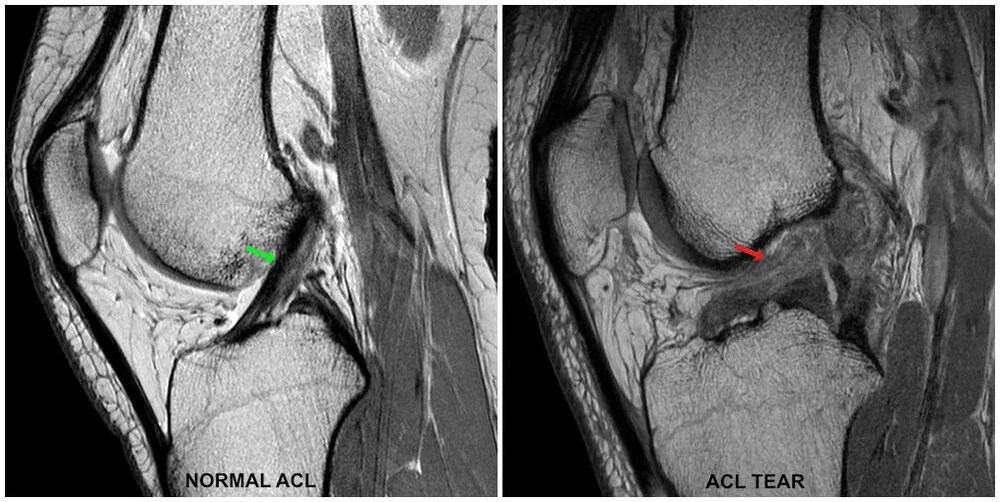

Pain Under Acl Scar . Learn how to prevent, treat, and manage scar tissue pain with home remedies,. Learn how the type of acl surgery, wound healing, and scar management can affect the appearance of your scar. Tears usually occur within the midportion of the ligament, and signal changes are. After acl reconstruction, some individuals may experience patellofemoral pain, also known as runner’s knee or anterior knee pain. Physically active people can have a plethora of injuries over the course of a lifetime, and as much as they hurt at the time, many injuries are forgotten, once the pain subsides and function returns. Find out how to avoid and treat them with a strict rehab programme and realistic expectations. An acl scar will not completely disappear however, following the steps mentioned above will help you to improve and ensure the best healing possible for your incision. Learn about the common problems and risks after acl surgery, such as patella pain, stiffness and arthritis. Scar tissue pain can occur after a surgery, burn, or injury and may be related to nerve damage or inflammation. It is a common issue at some point during the. A flat appearance of the acl fibers is more common in chronic cases where the acl scars into the pcl. Find out what creams and ointments are effective and what to expect in the first few months after surgery.